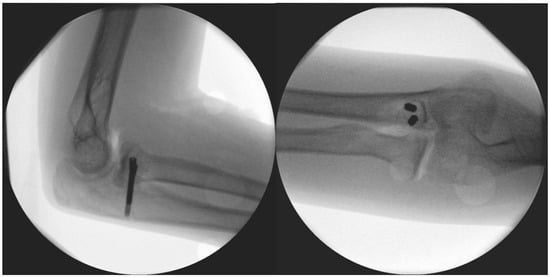

Diagnostic stability tests were carried out before and after reconstructive surgery, and, until then, an orthosis was provided to prevent the subluxation of the arm. Diagnostic tests were carried out prior to the planned operation under the influence of inhalation anesthesia. These included valgus stress in the 0- (extended), 30-, 60-, and 90-degree (°) positions, to which the medial ligamentous structures responded well by not letting the joint open or be subluxated. In the extended and 90° positions, the dorsally oriented stress test proved stable; however, in the 60° position during flexion, instability was noted, in which the joint was undoubtedly subluxated (Figure 3) while the summary of events can be found in Table 1.

Figure 3.

Results of diagnostic dynamic testing under fluoroscopy.

The surgery took place after disinfection and isolation, under general anesthesia, in exsanguinated conditions, and with prophylactic antibiotic protection (1 g Cefazolin) and took 90 min to complete. We used a ventral longitudinal incision along the anterior aspect of the elbow, following the modified Henry approach. After incising the skin and subcutaneous tissue, the bicipital aponeurosis was identified and carefully incised to expose the underlying brachial artery and median nerve, which were mobilized and retracted medially for protection. The biceps tendon was retracted laterally to enhance visualization. The brachialis muscle was then split longitudinally in line with its fibres, allowing access to the anterior joint capsule. Once the capsule was incised, the pronator teres was identified along its ulnar attachment and gently retracted, providing direct exposure to the coronoid process for reconstruction, facilitating precise debridement and accurate graft placement. The 2 × 1.5 × 3 millimetre (mm) bone fragment was removed. Histological analysis did not identify underlying pathology and proved that the fragment was otherwise formed of healthy bone tissue. The autograft was obtained from the iliac ala. From here, a 1 × 1 × 1 centimetre (cm) corticospongious piece was borrowed and reattached to the refreshed spongious surface of the coronoid process with two, one 26 and one 28 mm in length, A-spire (Sanatmetal Ltd., Eger, Hungary) screws (Figure 4). The graft size was determined based on the intraoperatively measured defect and used to restore anatomical height and contour to ensure joint congruity and stability. The recipient site was refreshed to gain access to a fresh vascular supply for graft incorporation with the help of a Volkmann spoon. A drain was applied, and after the reconstruction of the superficial layers, the skin was sutured. No additional reconstruction or reinforcement was needed for the median collateral ligament (MCL), as both the anterior and posterior maintained proper ligamentous integrity during the stability test. After swathing and bandaging, a 90° cast was applied, which was utilized for one month.

Figure 4.

Immediate post-op images of the fixation.